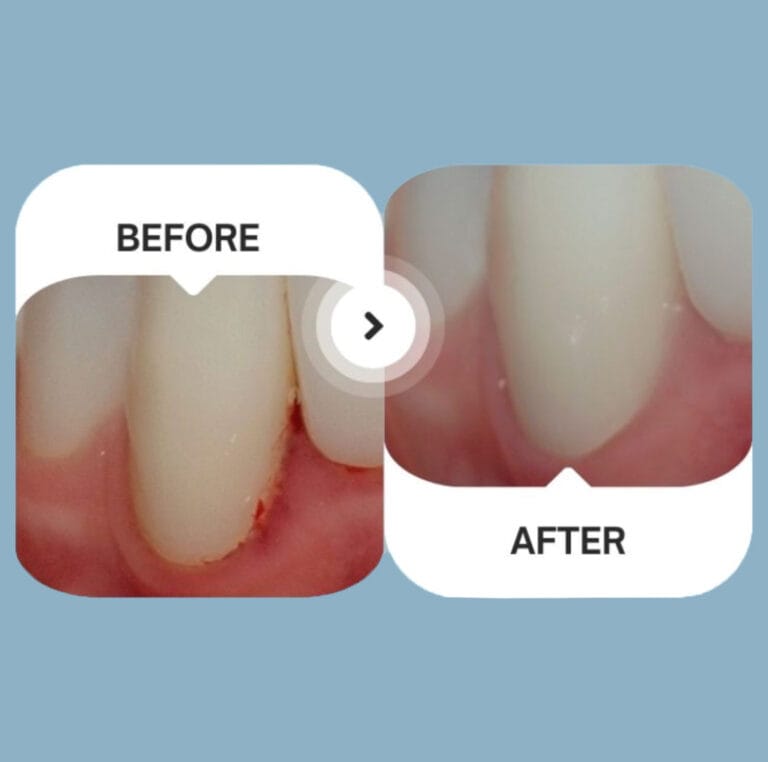

Sichtbar gesünderes Zahnfleisch

Bereits nach einem Monat!*

*Patient M, 38 Jahre alt

Klinische Studie, London, 2018

Sichtbar gesünderes Zahnfleisch

Bereits nach einem Monat!*

*Patient M, 38 Jahre alt

Klinische Studie, London, 2018